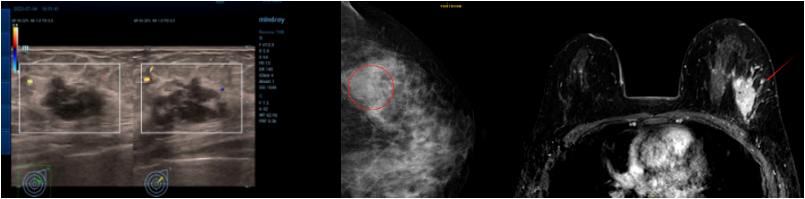

乳腺彩超:左侧乳腺实性结节(1-2点),28×18mm,BIRADS 4B类。左侧腋窝淋巴结肿大,15×11mm。

乳腺钼靶:左乳外上象限钙化灶及结节影,BI-RADS 4B类。

乳腺MRI:左乳外上象限肿块,大小约29mm×19mm,考虑乳腺癌,BI-RADS 6类。

乳腺彩超:左侧乳腺皮肤水肿增厚,约4.7mm。左乳部分切除术后,皮层明显增厚,左乳内结构显示不满意,BIRADS 0。右侧乳腺未见明显占位病变,BIRADS 1类。左侧腋窝区未见异常淋巴结。右侧腋窝淋巴结肿大,最大约33×15mm,皮质明显增厚,部分门型结构消失,性质待查。

乳腺MR:左乳上象限乳腺癌治疗后改变,病灶范围较前增大,较大范围约30mm×31mm×29mm;左侧乳腺多发结节、乳晕、皮肤增厚及右腋窝增大淋巴结,大者直径24mm,考虑转移。右乳多发囊性病灶,右乳背景多发轻度强化,考虑良性改变,BI-RADS 3类。

皮肤活检,病理:表皮大致正常。真皮浅、中、深层血管、淋巴管内见肿瘤细胞团块,胞核深染,胞浆丰富,部分呈空泡状。符合皮肤转移癌(乳腺来源可能)。免疫组化:ER(-),PR(-),HER-2浸润癌(2+),Ki-67约80%(+),TROP2(约50%中-强+、约20%弱+);GATA-3(+),TRPS1(+)。Fish阴性

乳腺组织穿刺,病理:乳腺浸润性癌。IHC:ER(-),HER-2浸润癌(1+),Ki-67热点区约80%(+),PD-L1(22C3)CPS为5,TROP2约90%中-强(+),E-Cadherin(+),P120膜(+),CK5/6(-),P63(-),Calponin(-),SMMHC(-),EGFR约80%中-强(+),TRPS1(+)。